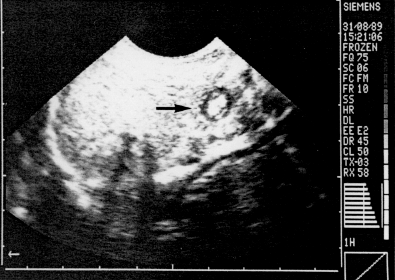

In transverse section the normal pylorus presents as a hypoechoic ring with a central echogenic core, resembling a "doughnut" or "target" (Fig. 10.1). By comparing sonographic images with histological sections Blumhagen and Coombs (l98l) were able to show that the hypoechoic ring coresponded to the muscular layer in the wall, while the more echogenic central core was formed by the mucosal and submucosal layers, including the muscularis mucosae. On these views the overall diameter of the ring, as well as the thickness of the sonolucent muscular layer, could be measured. The width of the hypoechoic muscular layer in normal infants between the ages of 2 and 10 weeks, was found to be approximately 3.0 mm.

| Fig. 10.1. Transverse ultrasonic section of normal pyloric ring showing "doughnut" (arrow). The hypoechoic ring is the muscular, and the inner echogenic core the mucosal/submucosal component of the ring |